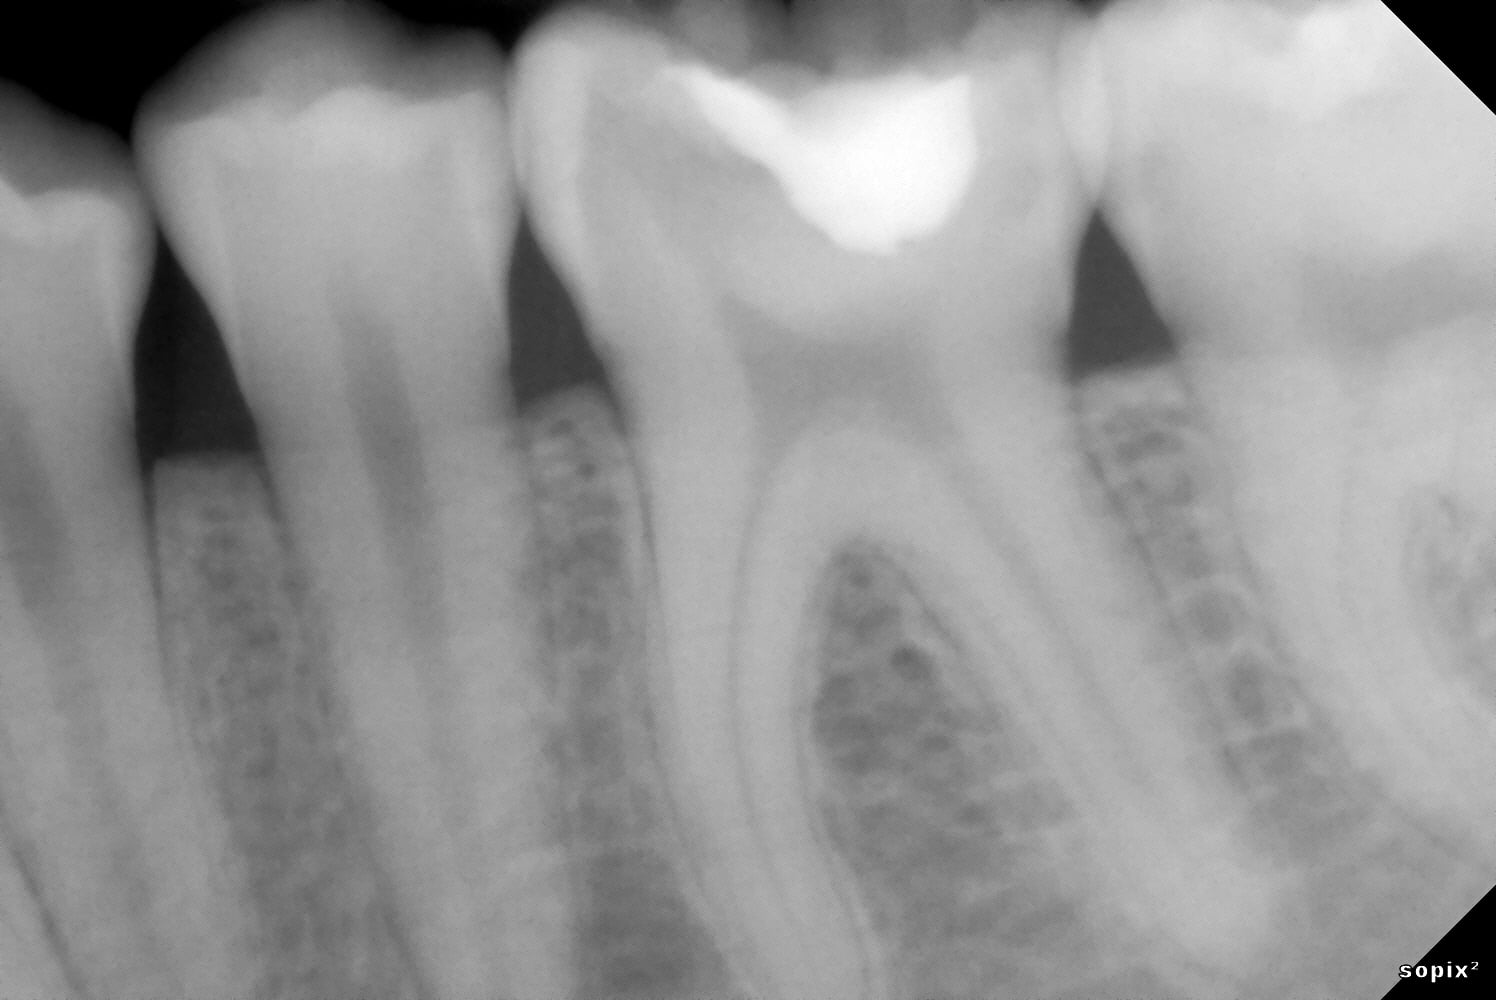

12-month follow-up

Digital volume tomography (DVT) and clinical photographs taken 12 months after treatment show a stable condition of tooth 36 following partial pulpotomy. Sensitivity testing, percussion testing, and circular probing of the surrounding gingiva confirm that both pulp vitality and periodontal health were successfully maintained thanks to Komet BioRepair.

The stages of a partial pulpotomy in pictures